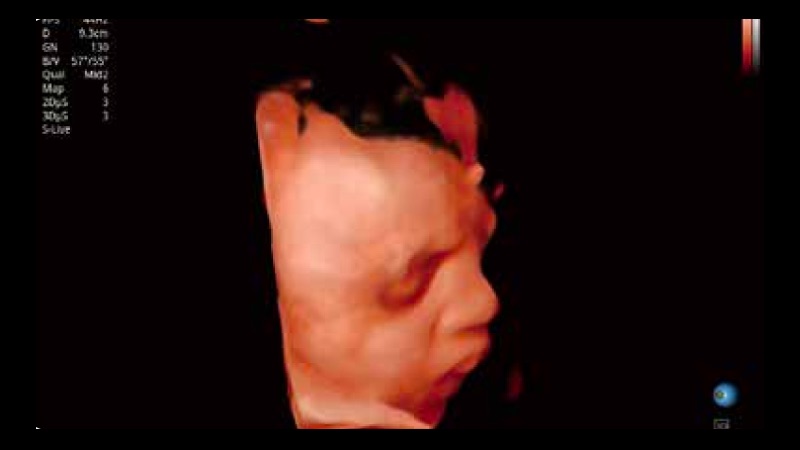

S-Live 高分辨率容积成像

通过仿真成像技术对3D/4D立体数据进行渲染,多种初始光源位置可选,并支持轨迹球360°光源位置自由调节,清晰显示不同方位容积图像细节。

临床图像